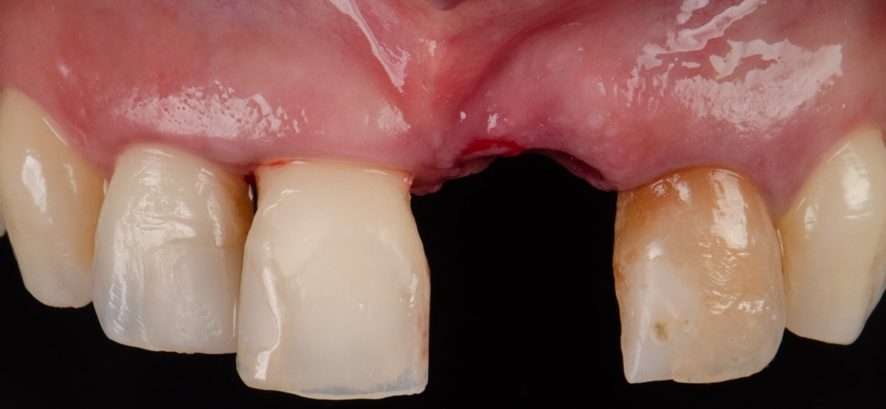

Aspecto inicial intra-oral:

Após exame clinico e tomográfico, foi observado comprometimento periodontal e trinca radicular no dente 21.

Após a confecção da guia cirúrgica pela Odontoplanning Brasil®, foi então realizado a exodontia do elemento 21.